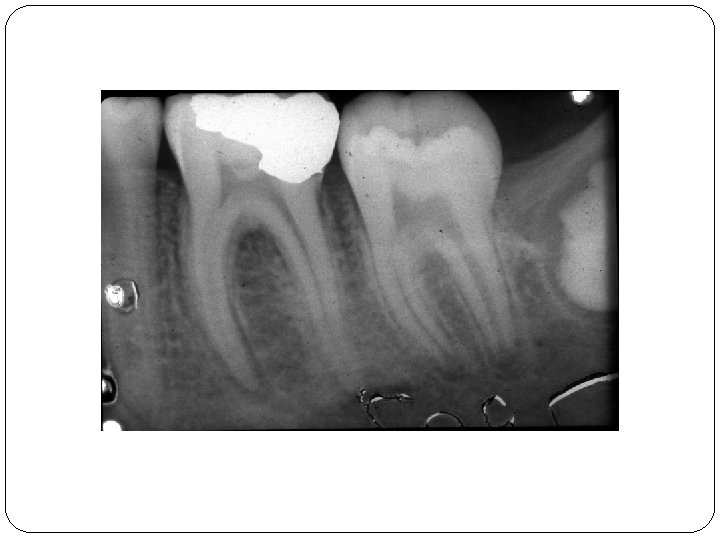

Wurzelbehandlung

Vor der Wurzelbehandlung Nach der Wurzelbehandlung